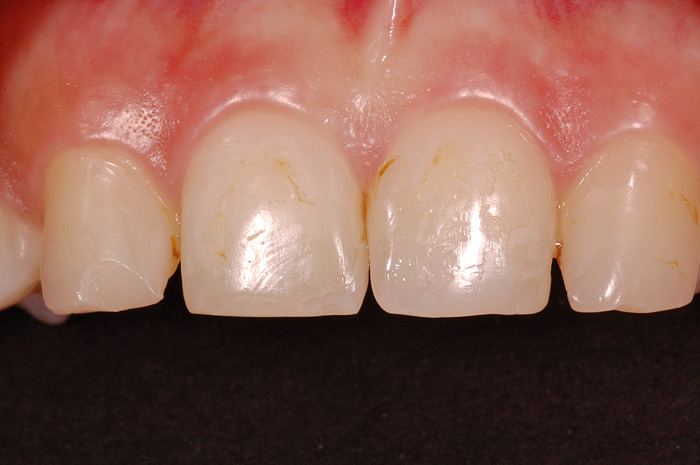

Fallbeispiel

Zum Vergrössern klicken